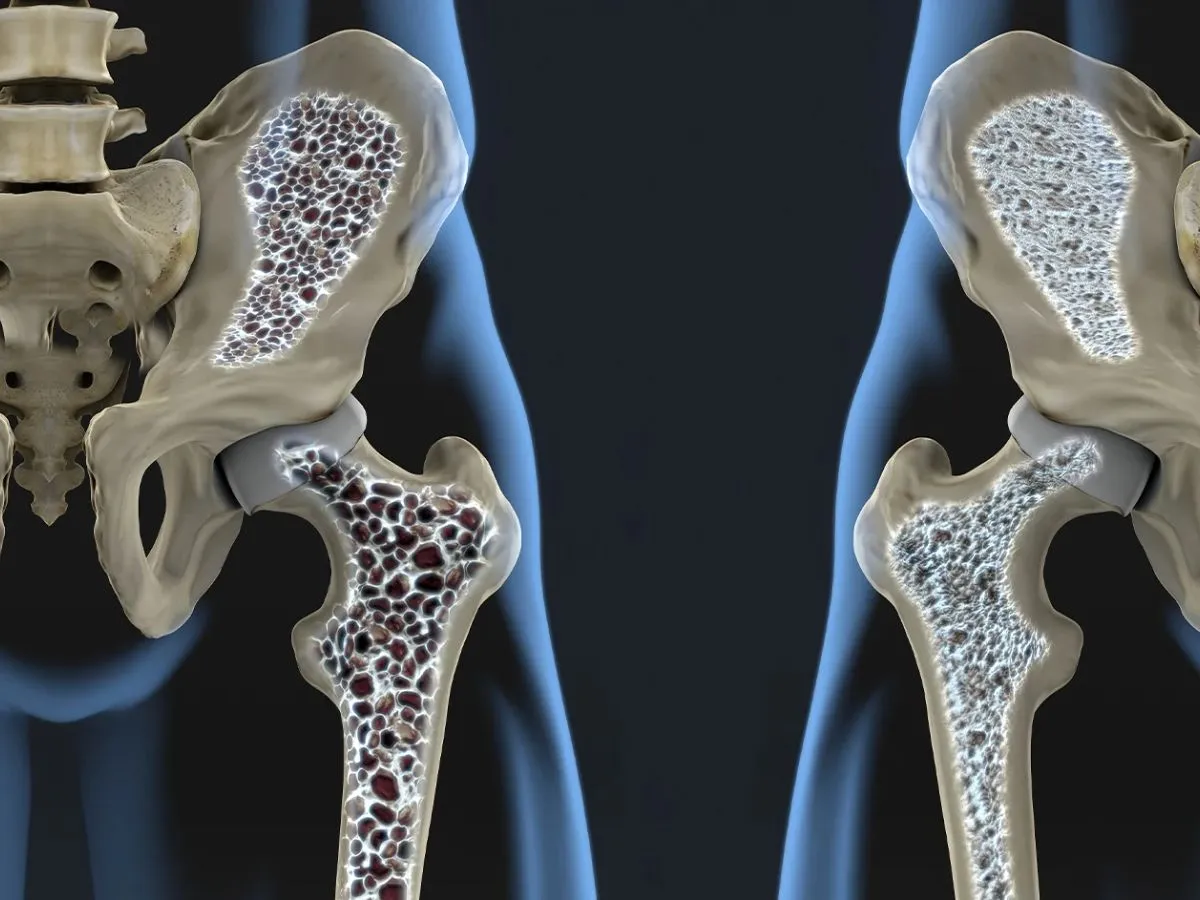

پوکی استخوان (استئوپروز)؛ نقش حیاتی کلسیم و ویتامین D در حفظ استحکام اسکلت بدن

پوکی استخوان به عنوان “بیماری خاموش” شناخته میشود، زیرا تا زمانی که یک استخوان (معمولاً در مچ دست، لگن یا ستون فقرات) دچار شکستگی نشود، هیچ علامت ظاهری ندارد. استخوان یک بافت زنده است که مدام در حال بازسازی است، اما با افزایش سن، تخریب استخوان از ساخت آن پیشی میگیرد. در این میان، کلسیم و ویتامین D دو رکن اصلی برای جلوگیری از این فرآیند و حفظ تراکم استخوانی هستند.

نقش در بدن: اگر سطح کلسیم خون پایین بیاید، بدن برای انجام عملکردهای حیاتی (مثل ضربان قلب و انقباض عضلات)، کلسیم را از مخزن استخوانها برداشت میکند که این کار باعث ضعیف و متخلخل شدن آنها میشود.